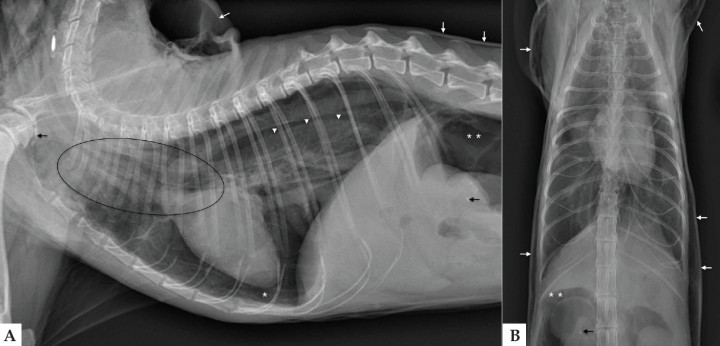

El análisis de sangre no reveló anomalías significativas. Se realizaron radiografías lateral derecha y ventrodorsal de la cavidad torácica (Fig. 1).

<p>Radiografías de tórax en proyección lateral derecha (A) y ventrodorsal (B) en un gato Persa de 15 años con un cuadro de disnea y enfisema subcutáneo.</p>

Figura 1

Radiografías de tórax en proyección lateral derecha (A) y ventrodorsal (B) en un gato Persa de 15 años con un cuadro de disnea y enfisema subcutáneo.

En la proyección lateral derecha del tórax (Fig. 2A) se observa una mejor visualización de las estructuras mediastínicas craneales, incluyendo la pared traqueal, el esófago y los vasos sanguíneos, al aparecer rodeadas por gas. Los hallazgos son sugerentes de neumomediastino. También se observa desplazamiento dorsal de la silueta cardiaca por una banda de opacidad gas y retracción del lóbulo pulmonar caudal, compatible con neumotórax. Hay aumento de la densidad radiológica del pulmón, posiblemente por atelectasia pulmonar secundaria.

<p>Mismas imágenes que en Figura 1. Proyección lateral de tórax (A): Neumomediastino (elipse); neumotórax (asterisco blanco) con retracción del lóbulo pulmonar caudal (cabeza de flechas blancas); enfisema subcutáneo (flechas blancas) y neumoretroperitoneo (doble asterisco blanco). Osteofitos o artrolitos a nivel de las articulaciones escapulohumerales y pequeñas mineralizaciones a nivel de las siluetas renales (flecha negra). En la proyección ventrodorsal (B) realizada tras drenaje del neumotórax se observa mayor distensión pulmonar.</p>

Figura 2

Mismas imágenes que en Figura 1. Proyección lateral de tórax (A): Neumomediastino (elipse); neumotórax (asterisco blanco) con retracción del lóbulo pulmonar caudal (cabeza de flechas blancas); enfisema subcutáneo (flechas blancas) y neumoretroperitoneo (doble asterisco blanco). Osteofitos o artrolitos a nivel de las articulaciones escapulohumerales y pequeñas mineralizaciones a nivel de las siluetas renales (flecha negra). En la proyección ventrodorsal (B) realizada tras drenaje del neumotórax se observa mayor distensión pulmonar.

Se aprecia gas en la región del cuello que se extiende a lo largo de la pared torácica y abdominal, compatible con enfisema subcutáneo, así como en área retroperitoneal craneal, indicativo de neumoretroperitoneo. Como hallazgos incidentales se visualizan osteofitos o artrolitos a nivel de las articulaciones escapulohumerales, compatible con osteoartrosis, y pequeñas mineralizaciones a nivel de las siluetas renales.

Tras el drenaje del neumotórax se realiza la proyección ventrodorsal (Fig. 2B), ya que la disnea que presentaba el paciente previamente dificultaba realizar proyecciones adicionales. En la imagen se puede observar una mayor distensión pulmonar.